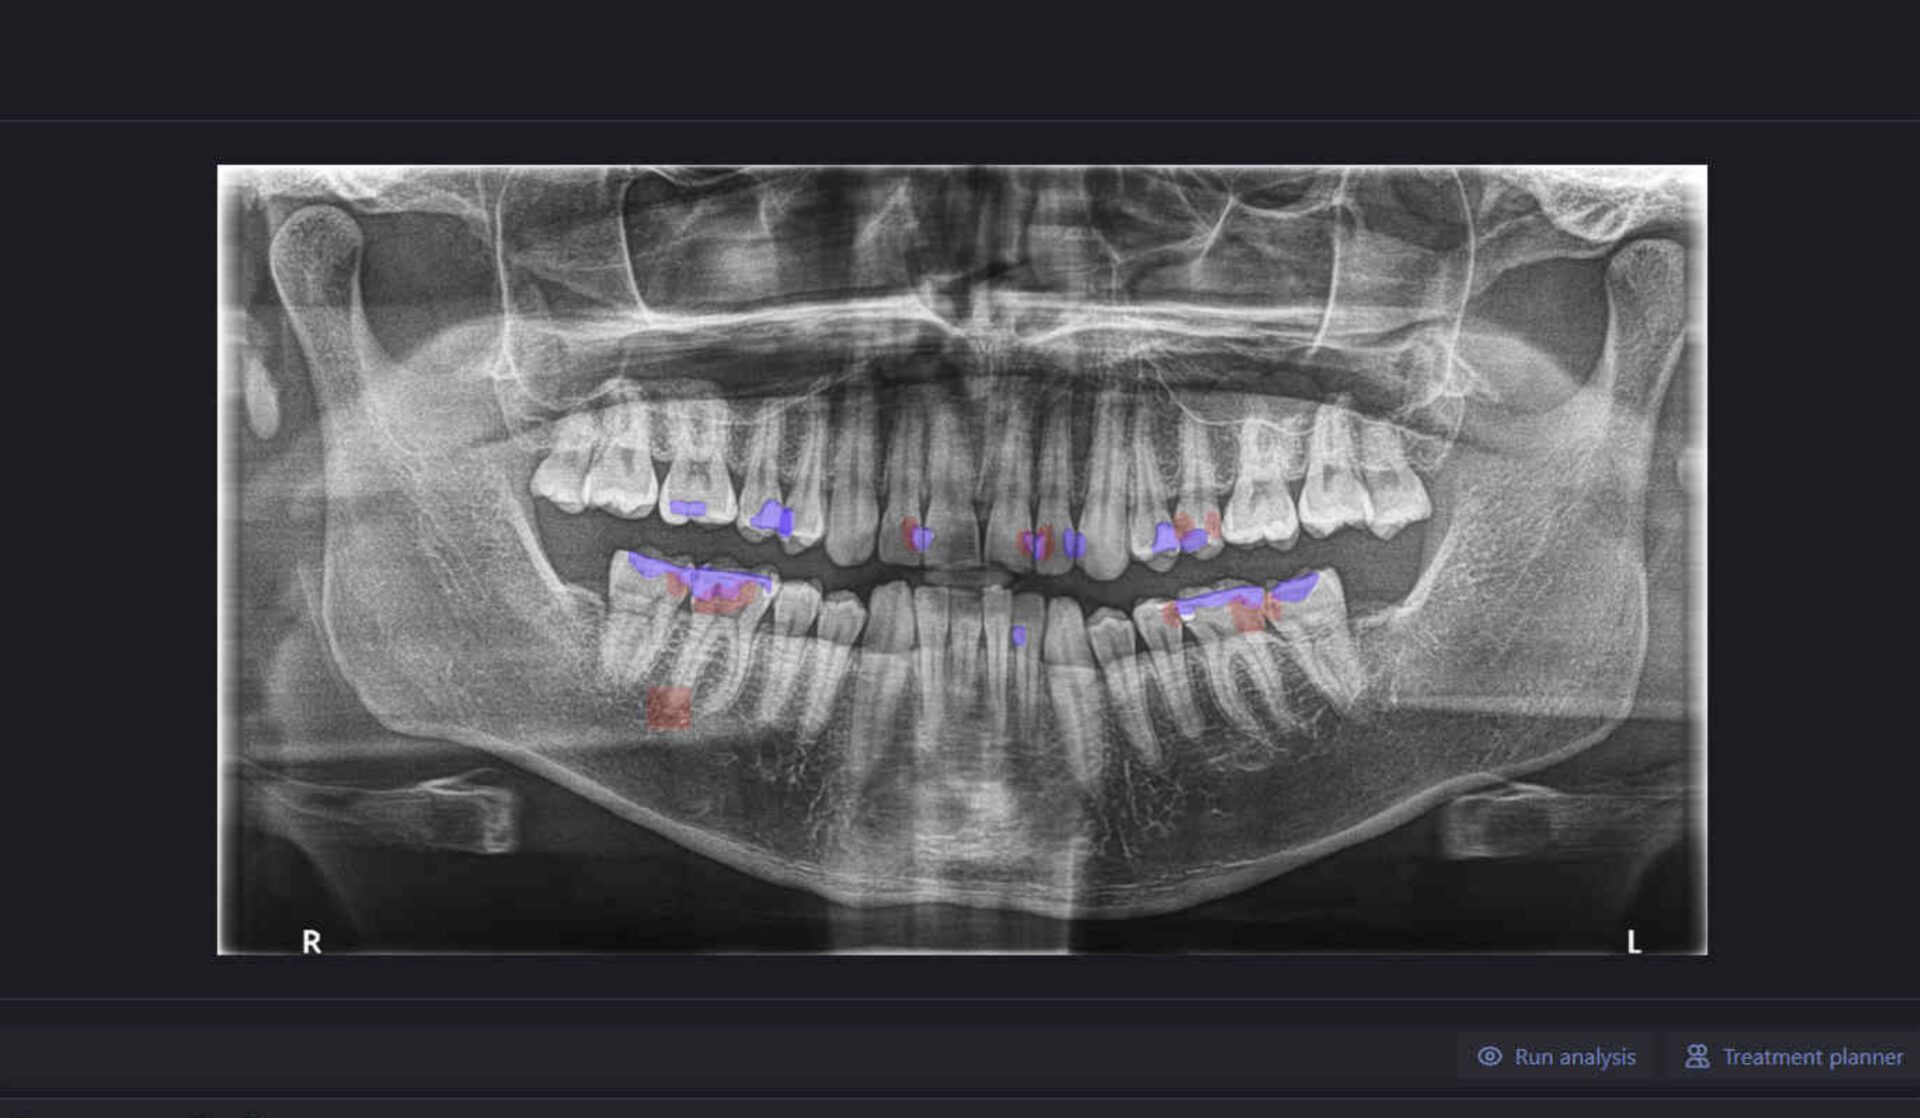

Dental diagnostics and productivity software utilizing AI to boost clinic profitability and improve patient communication and care.